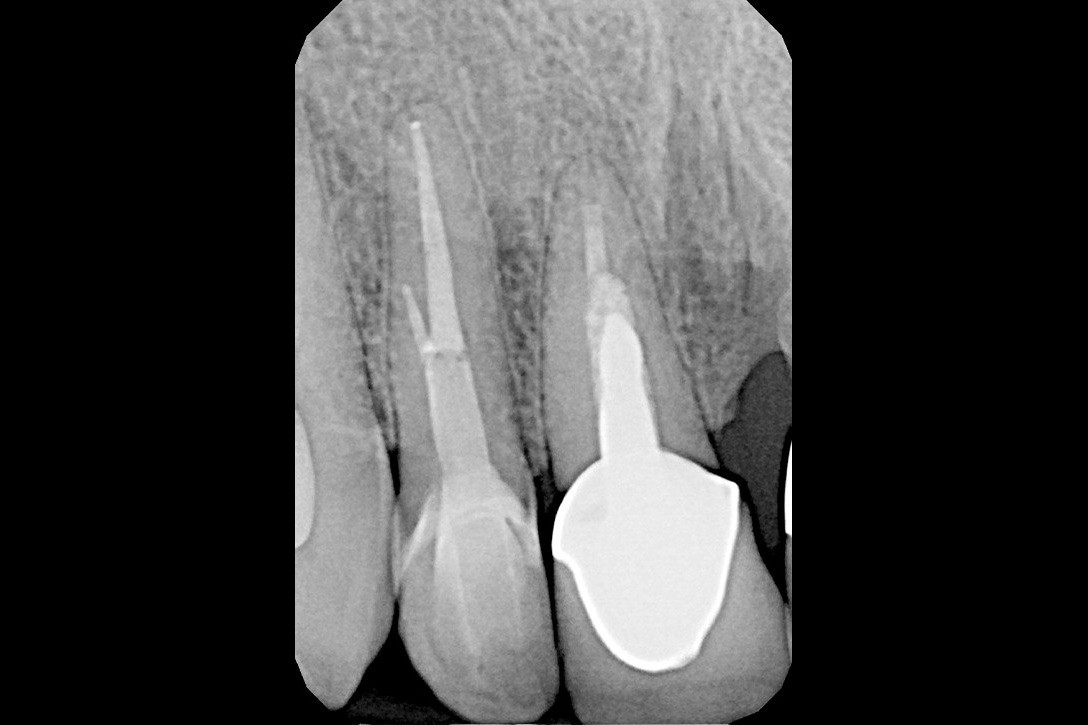

W przypadku zaawansowanych postaci zapaleń miazgi oraz zapalenia tkanek okołowierzchołkowych obraz radiologiczny jest warunkiem rozpoznania. W takiej sytuacji standardem diagnostycznym są zdjęcia przylegające zęba, często wykonywane przy użyciu radiowizjografii na fotelu stomatologicznym w trakcie leczenia zęba. Przydatne jest również badanie RTG OPG pantomograficzne, które pokazuje w dwuwymiarowym obrazie zarówno uzębienie, jak i cały układ kostny szczęki oraz żuchwy.

Na podstawie zdjęcia rentgenowskiego określa się kształt i długość kanału bądź za pomocą specjalnego urządzenia mierzy się jego długość. Potem lekarz otwiera wejścia do kanału, chroniąc ząb koferdamem, czyli specjalną gumą, zapewniającą sterylność oraz chroniącą przed środkami chemicznymi służącymi do oczyszczania kanału. Używa się do tego zarówno specjalistycznego sprzętu, jak i nowoczesnych mikroskopów, pozwalających na uzyskanie dokładnego obrazu leczonego zęba. Ostatnią czynnością jest wypełnienie materiałem światłoutwardzalnym i zabezpieczenie zęba przed dostaniem się i rozwojem bakterii mogących wywołać wtórny stan zapalny.

By uniknąć niedokładności leczenia, oprócz sumiennego wykonania procedur należy diagnostycznie kontrolować każdy etap leczniczy przy użyciu rtg. Szansą dla niedokładnie wypełnionego kanałowo zęba jest jego powtórne leczenie endodontyczne, zwane REENDO.

Leczenie kanałowe zęba pod mikroskopem daje lepszy wgląd w pole zabiegowe podczas odnajdywania i udrażniania kanałów korzeniowych oraz ich poszerzania i precyzyjnego wypełniania. Powiększony obraz ułatwia i przyspiesza pracę szczególnie przy niestandardowej anatomii zęba.